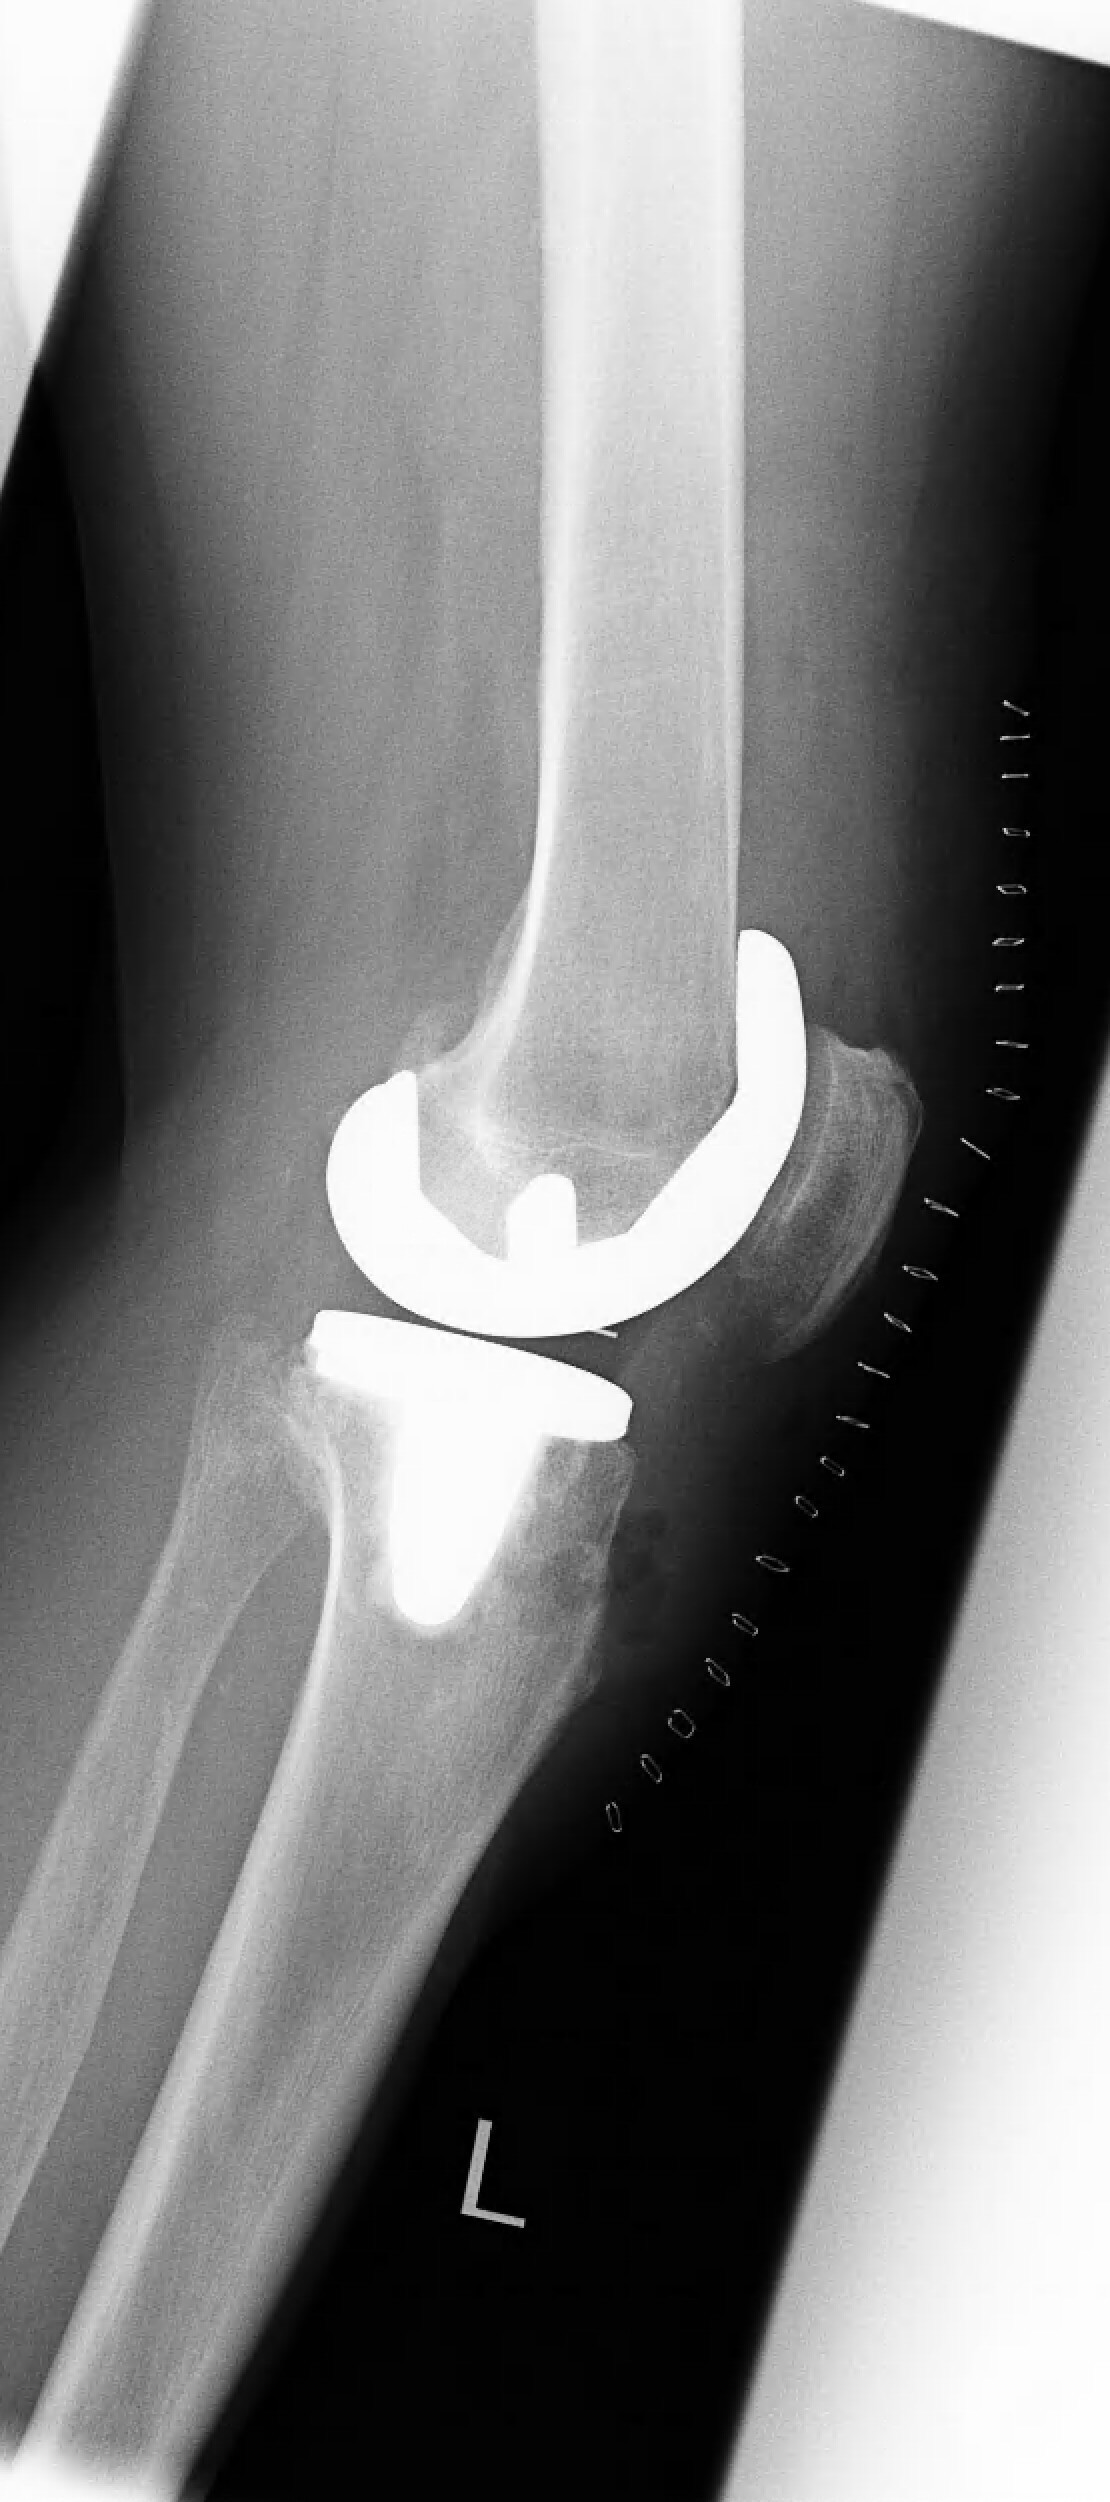

Nachdem die nicht operativen Therapiemaßnahmen (Krankengymnastik, korrigierende Einlagen, Spritzentherapie) ausgeschöpft waren und die Lebensqualität anhaltend beeinträchtigt war, wurde die Patientin über die Option eines künstlichen Kniegelenks (KnieTotalEndoProthese = KTEP) informiert. Mithilfe eines Oberflächenersatzes (Typ „Doppelschlitten“) konnte die abgenutzte Knorpeloberfläche überkront und gleichzeitig die korrekte Beinachse wiederhergestellt werden. Das Ganglion wurde über den gleichen OP-Zugang erfolgreich entfernt.

Nach erfolgter Rehabilitation (1 Woche Klinikaufenthalt, 3 Wochen Reha-Klinik und 8 Wochen ambulanter Physiotherapie) hat die Patientin in der Zwischenzeit Dank des künstlichen Kniegelenks ihr gewohntes Aktivitätsniveau im Alltag erreicht und freut sich, schon bald wieder auf dem Tennisplatz stehen zu können.